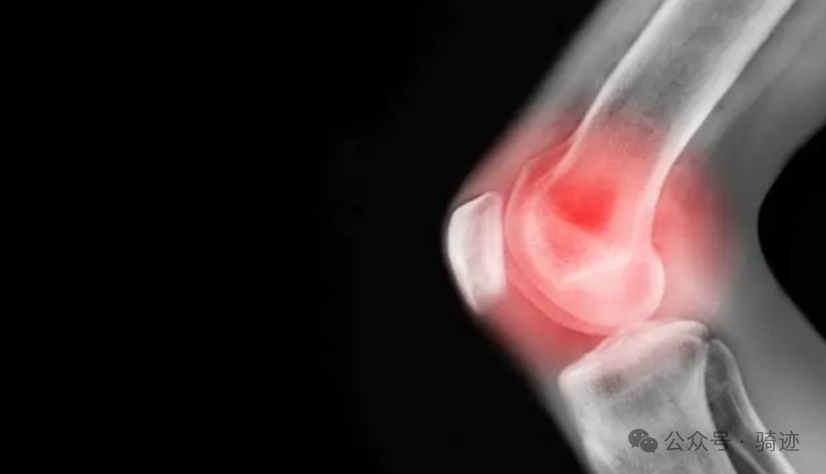

据了解,目前全世界关节炎患者有3.55亿人。亚洲地区每六个人中就有一人在一生的某个阶段患上关节炎。在中国,估计目前关节炎病人达1亿以上,随着老龄人口的增长,关节炎患者还在不断增加。为此,世界卫生组织把每年的10月12日定为国际关节炎日,以此提醒人们,对关节炎要早预防、早诊断、早治疗,防止致残。因此我们在锻炼的时候,除了要适度,还要注意选择合适的锻炼方式,减少对关节的冲击,比如:骑行、游泳等。尽量减少增加关节扭力或关节面负荷过大的运动,如爬山、长时间健步走或下蹲起立等活动。

第一,骑单车平顺且力度均衡的踩踏不会伤害到膝盖,可以有效降低膝关节劳损的风险。第二,与其他锻炼项目相比,骑单车对的肌肉组织分解和炎症影响更小,这也是为什么长跑运动员一般比自行车运动员更瘦更容易受伤,甚至腿部肌肉都没有自行车运动员发达强壮。第三,研究表明,人体运动后,血液的流动速度加快,就会产生一氧化氮,一氧化氮的功用,就是可以让包围在血管周围的肌肉变得柔软。血液的流动速度愈快,产生的一氧化氮也愈多。而骑单车可以让血液的流动速度加快十倍。